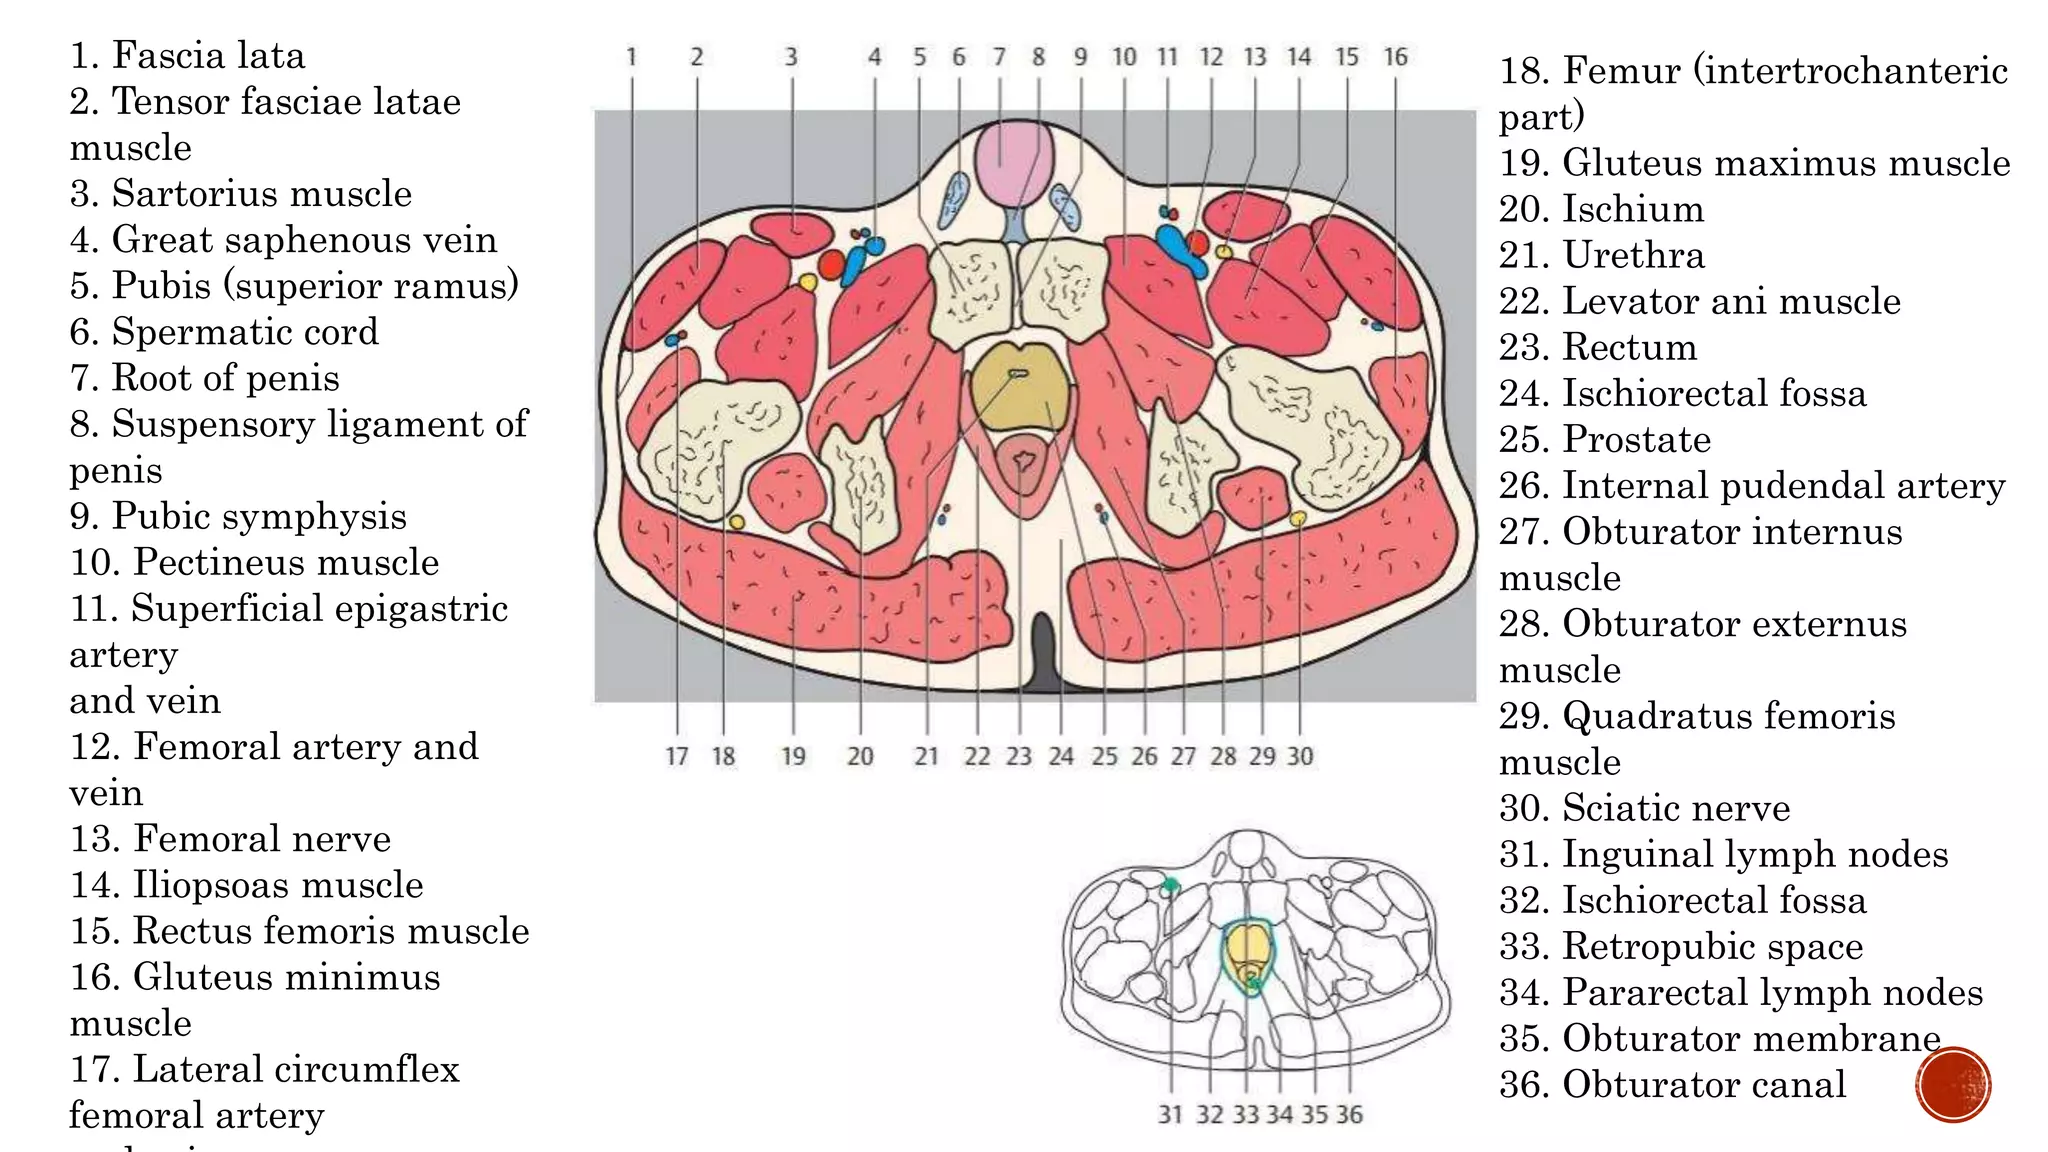

The document describes the anatomy of the abdomen and pelvis region of the human body. It lists over 40 structures and their locations, including major organs like the liver, kidneys, intestines, blood vessels and muscles of the abdominal wall and pelvis. The structures are grouped into sections focusing on different anatomical areas like the abdomen, retroperitoneum, pelvis and gluteal region.